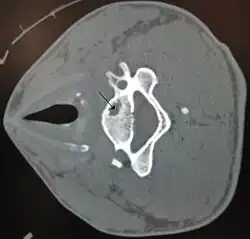

| A bone cyst in the vertebra of the neck as seen on CT | |

On CT scans, bone cysts that have a radiodensity of 20 Hounsfield units (HU) or less, and are osteolytic, tend to be aneurysmal bone cysts.[1]